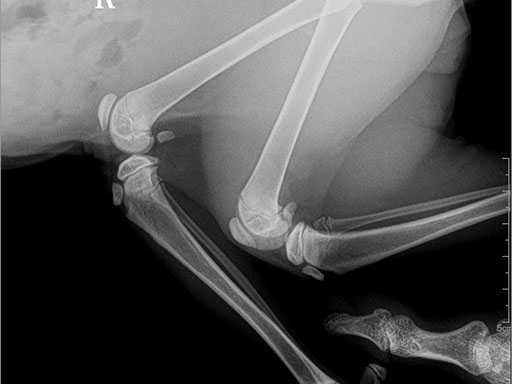

ЦИФРОВОЙ РЕНТГЕН В ВЕТЕРИНАРИИ